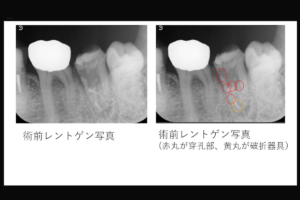

【穿孔部から異物の突出を認めた上顎右側中切歯の症例】「抜歯と言われたが、歯を残したい。」

穿孔部から異物の突出を認めた上顎右側中切歯の症例

治療内容:上顎右側中切歯 根管治療(穿孔修復、根尖孔外異物除去)